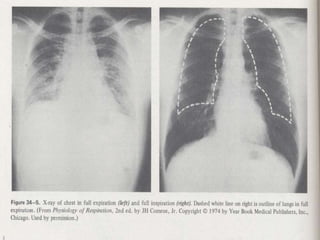

When the diagram contracts it forces

forward and the ribs lift outward.

Results in a reduction of intrapleural

pressure     expansion of the lungs